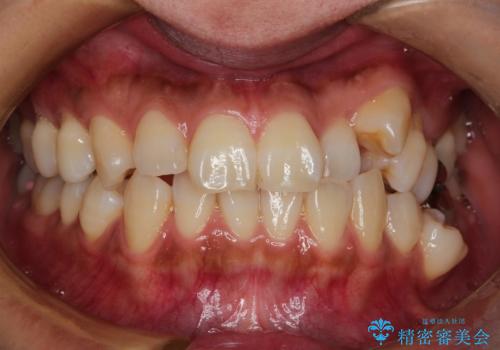

ハーフリンガル抜歯矯正 八重歯を改善する

- 小臼歯4本抜歯によるハーフリンガル・ワイヤー矯正を計画した。

シビアな八重歯がきれいに歯列にはいることにより、笑った時の印象などもかなり大きく変わります。